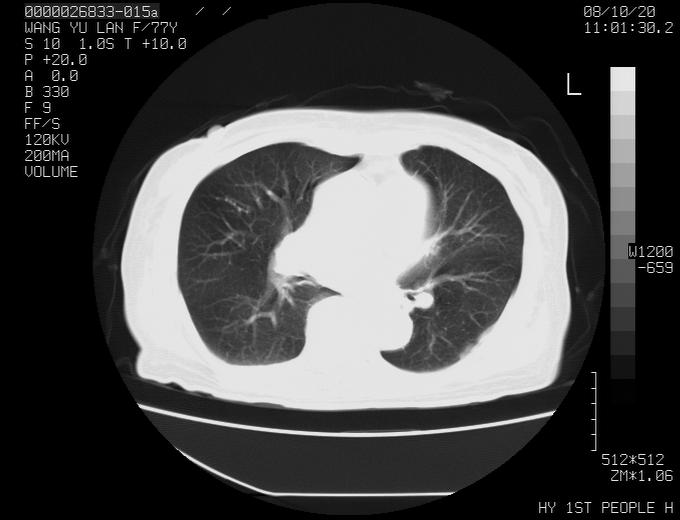

女性,77岁,胸部疼痛半月。左上肺团块影,本人考虑血管畸形,请分析

支持楼主,    但是做个矢冠状面成像就完美了

动脉期未见大血管同步强化,首先考虑周围型肺癌

动脉期病灶近中线侧可见星芒状与大血管同等强化密度,支持考虑血管畸形伴血栓形成,动脉期不曲型,不除外周围型肺癌

1、考虑avm可能性大。2、纵隔有肿大淋巴结,左肺上叶有炎性病变,不排除肺癌并转移可能。

左肺周围型肺癌并肺门淋巴结转移,很典型了!